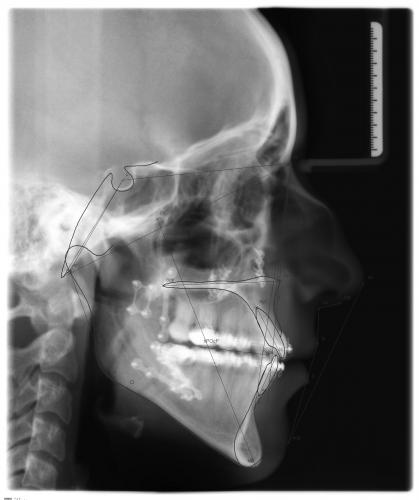

Röntgenbefund

Zu Behandlungsbeginn und nach der Operation

Die Verlagerung der Kieferbasen, v.a. im Unterkiefer, ist deutlich zu erkennen. Ferner sieht man auf dem rechten Bild die Metallplatten aus Titan, die die Knochenfragmente während der Heilungsphase in der gewünschten Position zusammenhalten. So wird frühzeitig sichergestellt, daß der Patient wieder normal kauen kann. Die Metallplatten können nach ca. 6 Monaten in einem Zweiteingriff entfernt werden.